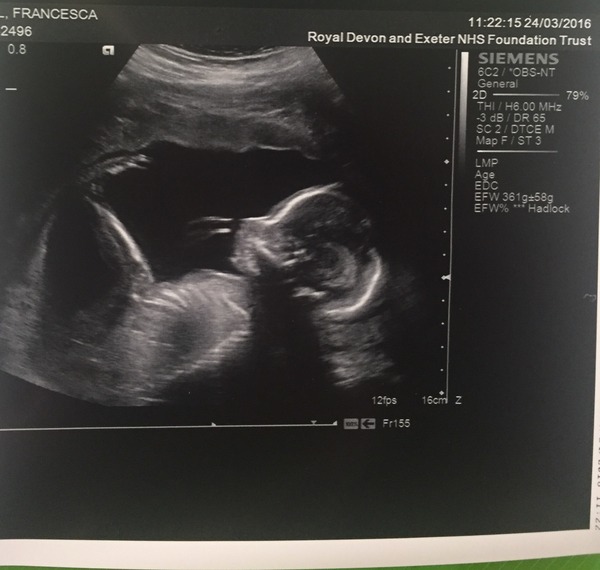

strandedabroad · 24/03/2016 21:23

Sorry guys, I forgot to crop my name out of the picture so I got the message deleted. I'll try again!

Oh Lily, what an ordeal. I hope the next few hours/days go smoothly and that you can relax a little.

Had my 20-week scan today, all was well. I'm in awe of all the details they can see. Still team yellow. Baby is chubby and had a longer than average femur length - we're both tall-ish, so that makes sense.

I still think boy, just based on the profile! Smile